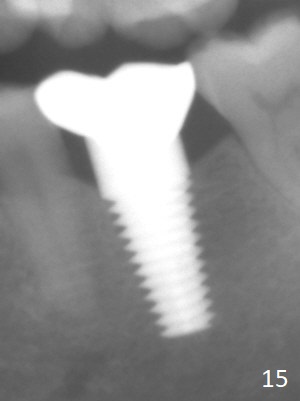

The Emax crown fractures 3.5 years post cementation; there is formation of the apparent lamina dura around the implant (Fig.13). There is no atrophy of papillae when the new crown is cemented (Fig.14 *). There is no bone loss nearly 4 years post cementation (Fig.15).